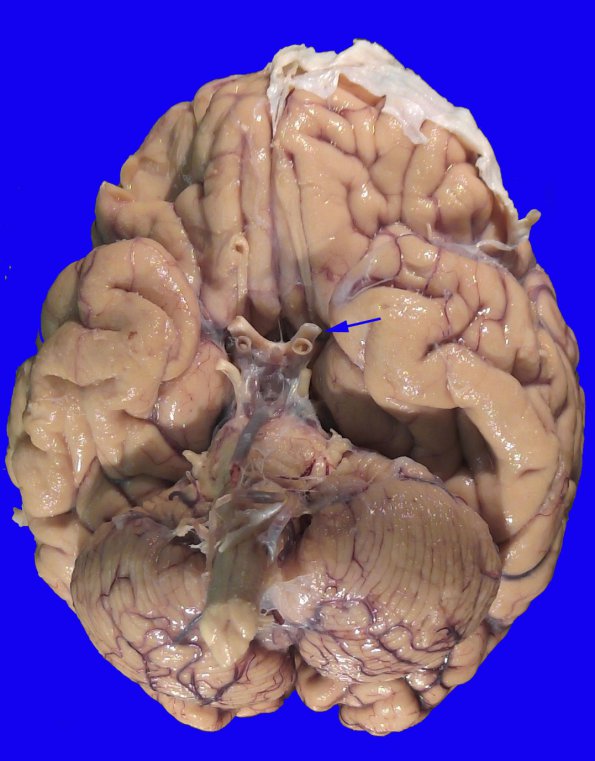

17B2,3 The ventral surface shows little substantial abnormality other than left optic nerve (arrow) discoloration, demyelination and atrophy.